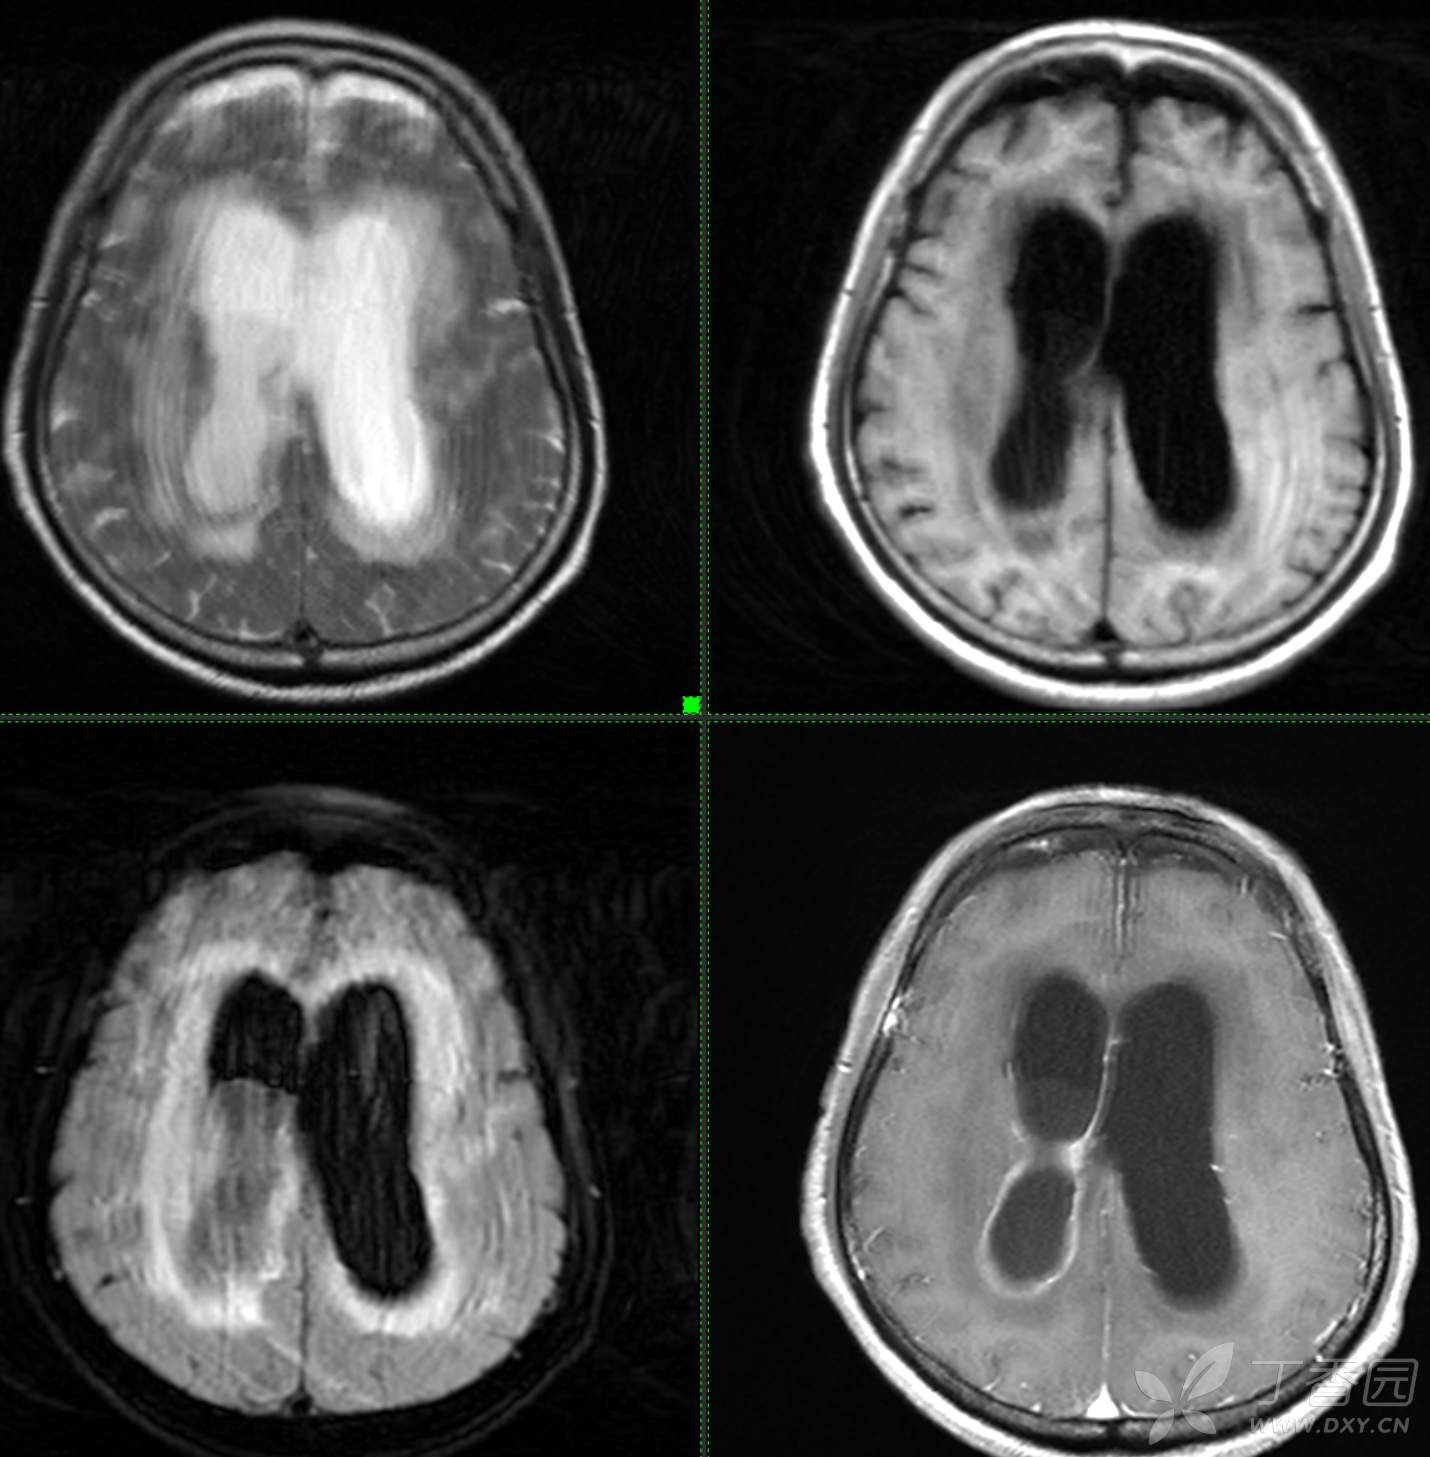

现病史: 患者3周前无明显诱因下出现头晕,无头痛,伴视物模糊,肢体乏力,走路步态不 稳,无意识不清,对答切题,当地医院查血常规示:中性粒细胞分类:77.7%.淋巴细胞分类:15.6%,中性性粒细胞分类:7.1*10^9/L.葡萄糖:22.35mmol/,头颅平扫示:右侧丘脑饱满,密度减低伴低密度灶,占位不排除,两侧半卵圆区、额叶低密度灶,以“1.糖尿病酮症酸中毒,2.颅内占位性病变”收入住院治疗,1周前住院期间出现发热,先后予抗感染,控制血糖等对症支持治疗,2天前无明显诱因下再次出现发热,伴血糖升高,自测体温40℃,血糖20mmol儿,伴气促无胸闷,袖志模糊,反应迟钝,无畏寒寒战,无腹痛腹泻等不适,昨日送至我院就诊